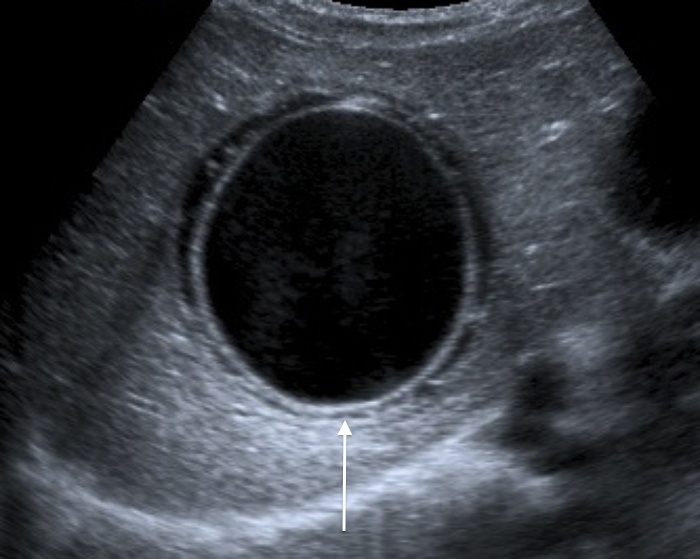

C

This one above turned out to be a hyatid cyst (Echinococcosis).